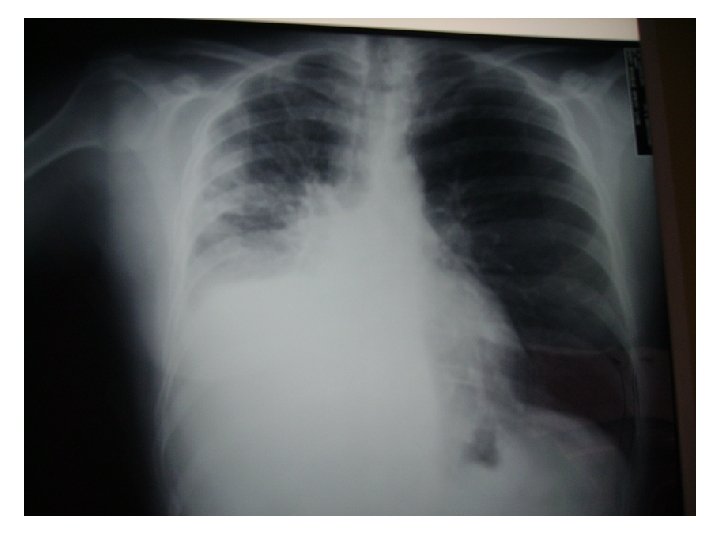

Exploraciones Rx de tórax: ocupación del seno costodiafragmático (¿derrame pleural? ) y masa hiliar derecha con elevación diafragmática homolateral. TAC tóraco-abdominal: gran masa mediastínica hiliar derecha (64 mm x 40 mm); amputación del bronquio principal derecho y afectación de la carina y tráquea en su tercio distal, con ocupación del bronquio lobar superior derecho y colapso completo del lóbulo medio e inferior derecho. La masa infiltra vena cava superior y arteria pulmonar. Se detectan adenopatías subcarinales y paratraqueales superiores e inferiores derechas de 16 a 25 mm, así como infiltrados periféricos en lóbulo superior derecho. En hígado hay tres nódulos hipodensos (segmento II y VI) de 7, 30 y 5 mm respectivamente, de significado incierto. La fibrobroncoscopia objetivó una tumoración que obstruía casi completamente el bronquio intermediario. El estudio histológico fue de adenocarcinoma pobremente diferenciado. El estudio de marcadores genéticos detecta una amplificación (FISS) del EGFr sin mutaciones y una sobre-expresión (en el rango superior de la normalidad) del BRAC 1.